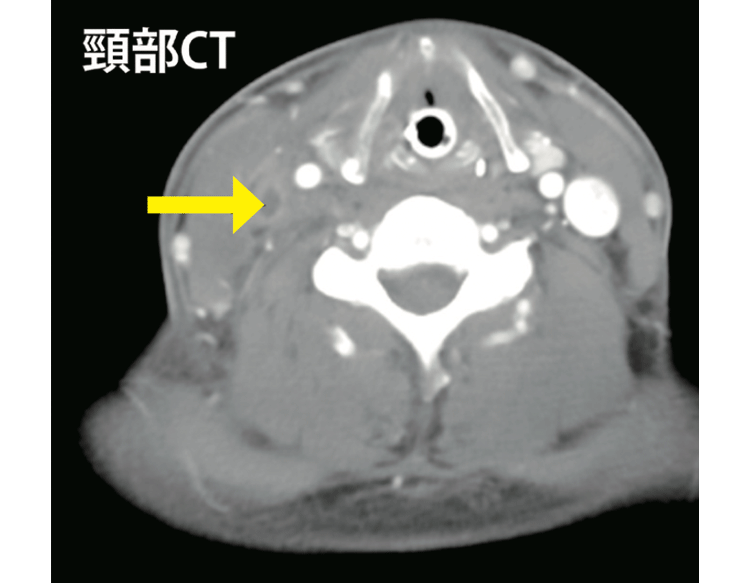

症例は30歳代男性。主な症状は40℃の発熱と咽頭痛(いんとうつう)(喉(のど)の痛み)。ニューキノロン系抗生物質(殺菌作用のあるもの)で改善せず紹介となりました。炎症反応が高く(白血球は16,800/μL(※1)、CRP(※2)は32mg/dL)、首のCTを撮影した直後に血圧90/59mmHgに低下しショック状態となり、呼吸困難となったため、人工呼吸器による管理を行いました。

原因として、右内頸静脈の内部に血栓(けっせん)(血液の塊(かたまり))を伴う膿瘍(のうよう)(膿(うみ))があり、採取したところ酸素がなくても発育する菌(嫌気性菌(けんきせいきん))を検出し、感染性血栓性頸静脈炎(けいじょうみゃくえん)(Lemierre〈レミエール〉症候群、図1)と診断しました。複数の抗生物質を8週間以上の長期間内服してもらうことで、ようやく治療が完了しました。

左側は頸静脈が造影されています。右側には血管が描出されない膿瘍塞栓があります